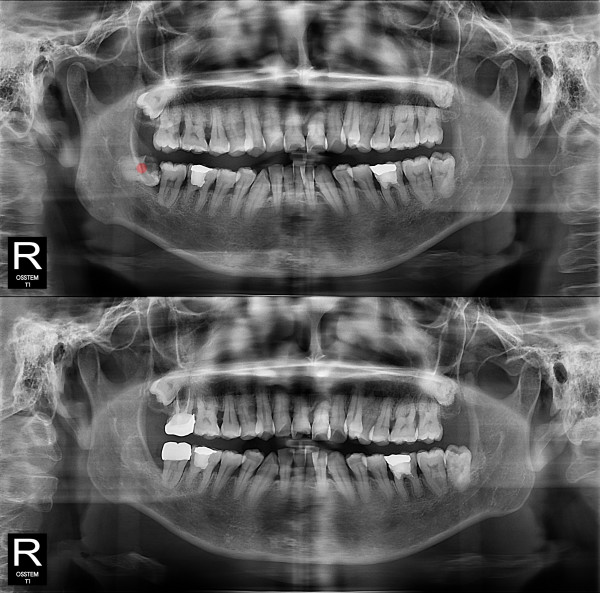

智齿拔除 严重龋坏的智齿